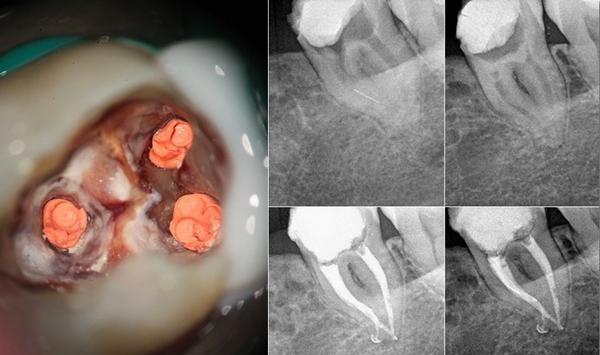

牙髓炎

伤及牙神经,受冷热酸甜等刺激时疼痛剧烈,不敢用凉水刷牙,不受外界任何刺激的情况下会突然发生剧烈疼痛,夜晚疼痛升级,常常因为牙痛难以入睡。

治疗方式:根管治疗+补牙+冠修复

根管治疗

根尖周炎

伤及牙神经,在牙髓炎症状的基础上,还会导致面颊部肿胀疼痛,使咬合无力、疼痛,甚至不能正常进食。

治疗方式:根管治疗+打桩+冠修复